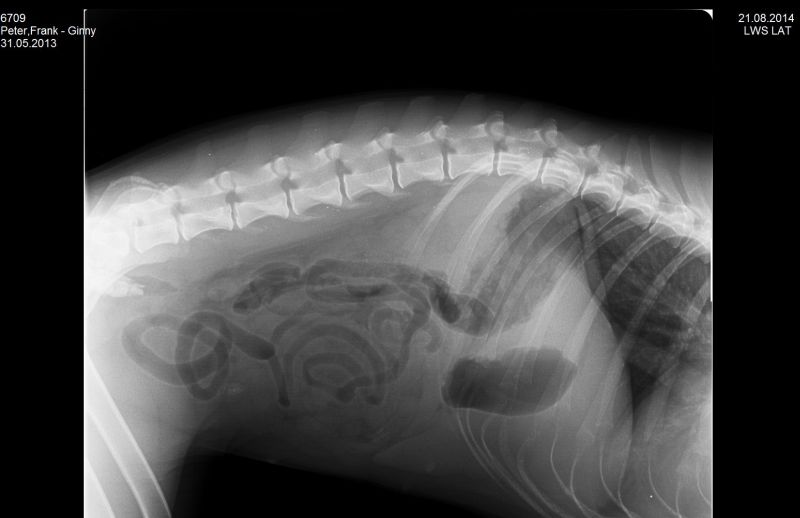

21.08.2014 - Ginny HD-und ED geröntgt - 15 Monate alt

24.08.2014 - Ginny - 15 Monate alt